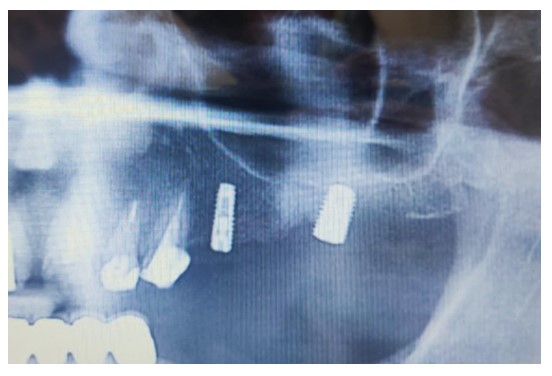

Two MegaGen ST implants (MegaGen Implant Company, South Korea) were placed. At the four-month follow-up, the maxillary first molar implant was exposed, with a significant periodontal pocket detected around it despite stability. OPG revealed bone resorption around the implant (Fig. 7), and CBCT identified a 0.5 mm radiopaque mass resembling residual roots. The implant was removed, the mass was excised, and the area was cleaned. Histological analysis confirmed osteosclerosis (Fig. 8).

OPG 6 months after surgery showing significant bone resorption around the dental implant.